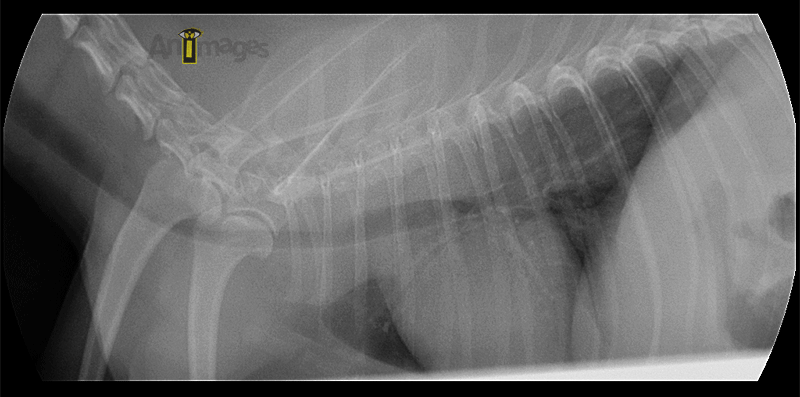

L’examen fluoroscopique effectué après palpation trachéale pour induire de la toux montre hors de tout doute un collapsus sévère affectant non seulement la trachée, mais aussi les bronches principales. L’implication des bronches est importante car elle limite la pose d’une prothèse endoluminale (stent), celui-ci ne pouvant être placé que dans la trachée et jusqu’à environ 1 cm de la carina.

Ces images proviennent de deux instants de la boucle fluoroscopique, illustrant la variation de diamètre important qui a lieu durant la toux chez ce petit chien. Notez le collapsus complete de la trachée (T) thoracique, de la carina et des bronches principales survenant durant cet épisode de toux.